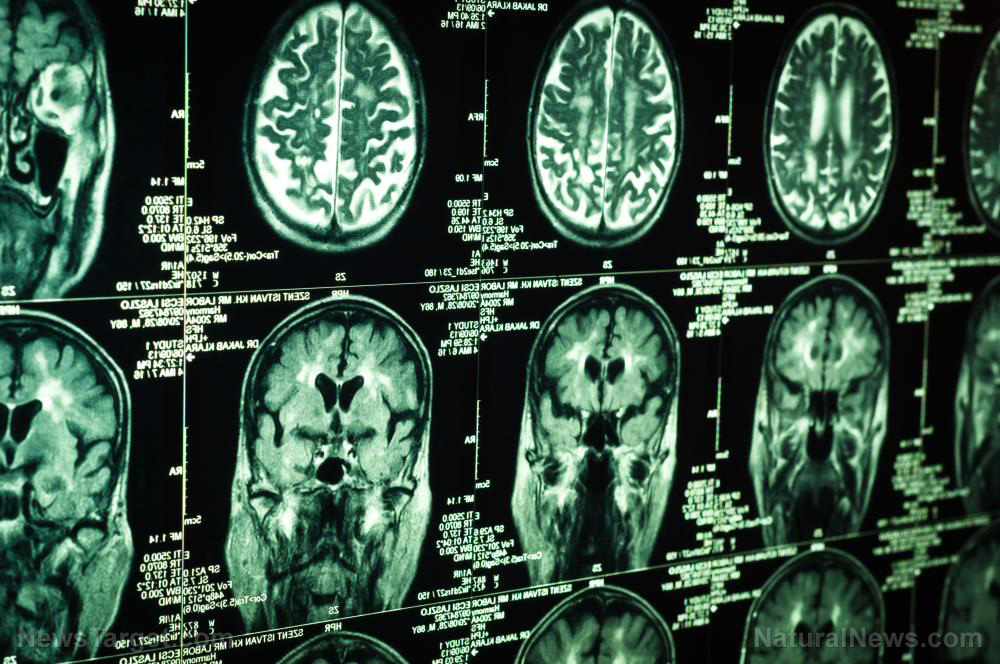

The latest protein maps of the brains of patients with Alzheimer’s disease showed that at least one region succeeded in holding off the ravages of the disease. U.K. researchers believed that the cerebellum’s ability to protect itself against Alzheimer’s might be reproducible in other parts of the brain.

They examined the brain and other essential organs of people who died due to complications caused by the neurodegenerative disease. To their surprise, the cerebellum of the patients lacked the distinct damage associated with Alzheimer’s.

In addition to the brains of people with Alzheimer’s, the Manchester researchers also looked at the organs of deceased people who died from cancer and other diseases unrelated to dementia. They compared the number and type of proteins found in six critical parts of the brain.

Lead researcher Dr. Richard Unwin and his teammates identified 5,825 different proteins present in the brain. Forty-four of these molecules were brand new ones.

Unwin’s team started their mapping study in the three brain regions that always came under attack by Alzheimer’s disease. The entorhinal cortex assisted in the preservation of memories, the cingulate gyrus handled emotions, and the hippocampus dealt with both emotions and memories. The hippocampus also tended to serve as the starting point for Alzheimer’s.

When they moved to the motor cortex and the sensory cortex, they found these areas more or less unaffected by dementia. The motor cortex oversaw movement, while its sensory counterpart regulated the senses used by the body.

Finally, the cerebellum proved untouched by Alzheimer’s disease. The proteins present in this pristine brain region could be the key to prevent the progress or onset of dementia in older people.